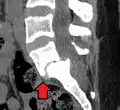

Anterolisthesis L5/S1. Blue arrow normal pars interarticularis. Red arrow is a break in pars interarticularis.